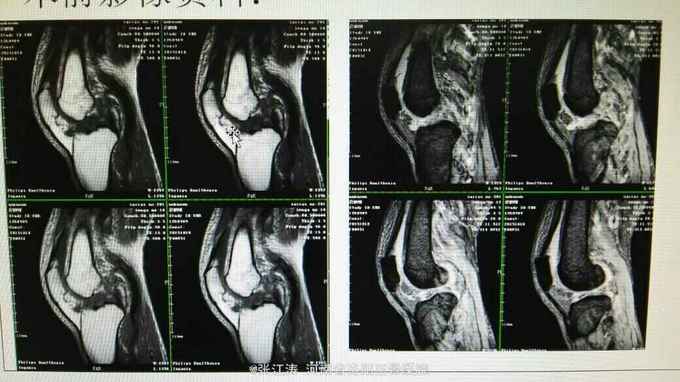

车祸致伤膝关节脱位3天住院,受伤后未做相应处理,仅行MRI检查。

膝关节前后抽屉试验及外翻应力实验阳性,末梢血液循环及感觉运动良好

膝关节脱位,前后交叉韧带损伤及内侧副韧带损伤